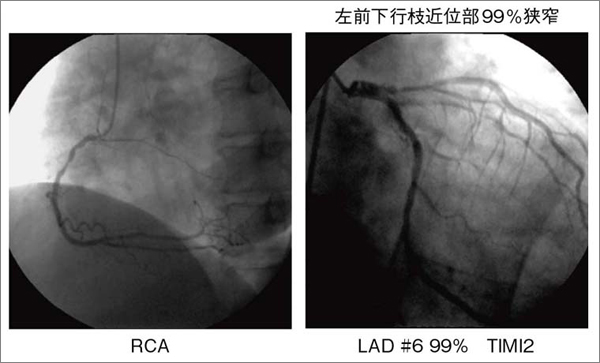

図3 不安定狭心症例の責任冠動脈狭窄率と99%狭窄病変に造影遅延を伴う群における心エコー壁運動評価

2007年4月〜2008年2月までに筑波メディカルセンター病院を受診した不安定狭心症212例のうち,造影遅延を有する99%狭窄の受診時心エコー壁運動評価。日常臨床では,壁運動異常なしと判定した領域が,冠動脈造影で造影遅延を伴う血流障害を有していることが稀ではない。

図4は,不安定狭心症の54歳,男性の2Dスペックルトラッキング解析画像である。本症例は,非典型的な安静時前胸部違和感を主訴に医療機関を受診した。心電図では前胸部誘導にST-T変化を認めるものの(図5),血液学的検査では心筋逸脱酵素の上昇はなく,心エコーでは明らかな左室局所壁運動異常は認められなかった。ところが,冠動脈造影では,左前下行枝近位部に99%高度狭窄病変と,末梢の造影遅延を認めた(図6)。冠動脈末梢の造影遅延は,冠血流量が低下していることを示す所見である。図4aに示す前壁中隔の全層radial strainは39%であり,図2の健常例の分布内に含まれる。また,同一症例のほかのセグメントのストレイン曲線とも大きな差異は認められない。ところが,図4 bに示すように,左前下行枝領域の内膜側radial strainは,カラー表示で青色で示され,ストレイン値は−3%と低値である。この結果,内膜側/外膜側radial srain比は非常に低値となった。これは,左前下行枝の灌流領域に一致する心内膜下収縮不全を検出している可能性がある。

図6 図4の症例の冠動脈造影所見

左前下行枝近位部に末梢の造影遅延を伴う99%狭窄を認める。